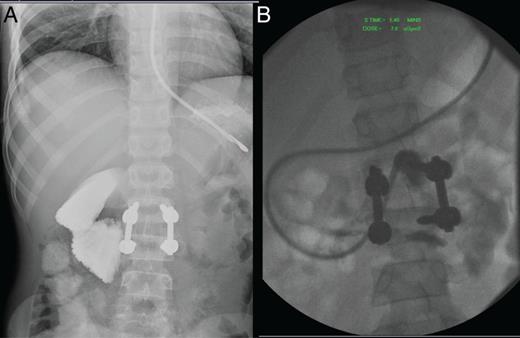

Over the next 4 days, his abdomen remained soft and non-tender. However, he progressively began to have small bilious vomits, and on Day 5, his abdomen was noted to be more distended. A repeat abdominal X-ray and CT was suggestive of acute obstruction with a transition point in the small bowel. He was taken for exploratory laparotomy on Day 5, which identified an internal herniation of jejunal loops through a mesocolic laceration (Fig. 1). There was a short segment of involved jejunum, which was slightly narrower in calibre but patent and well perfused and left in situ after reduction and repair of the mesocolic defect.

Intra-operative pictures (A) internal hernia of jejunal loop resulting in small bowel obstruction with proximal bowel dilatation. (B) Mesenteric defect in mesocolon. (C) Subsequent stricture in area of jejunal loop previous caught in mesenteric defect.